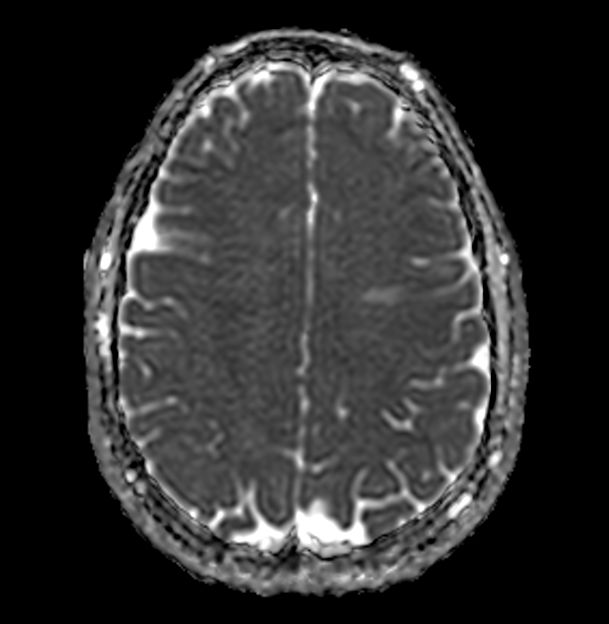

Axial Diffusion (ADC)

-